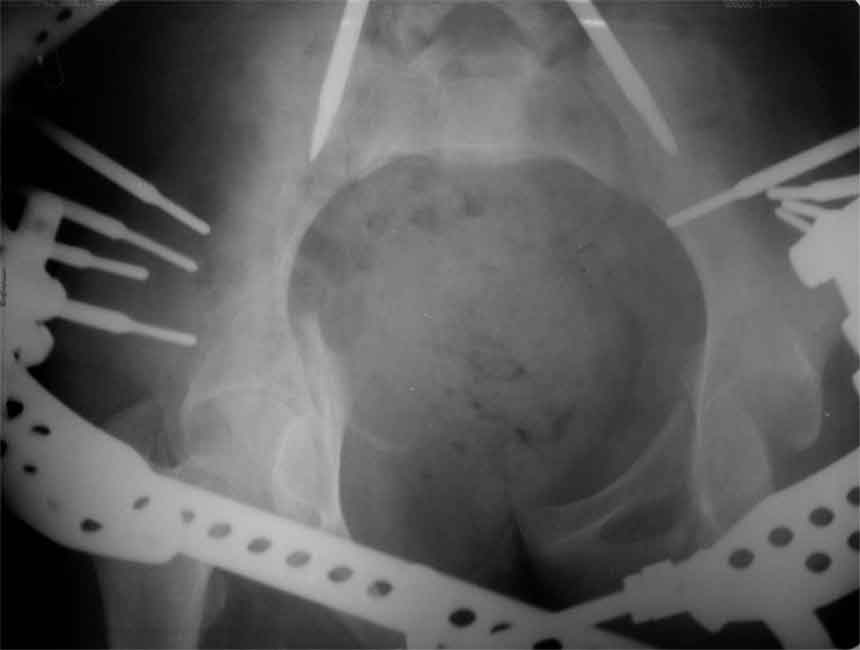

продолжение темы. не увидел энтузиазма в обсуждении. Вопросы прежние, первым этапом закрыто устранили вертикальное и передне-заднее смещение. Каким образом восстановить целостность тазового кольца, из каких доступов? Снимки в приложении